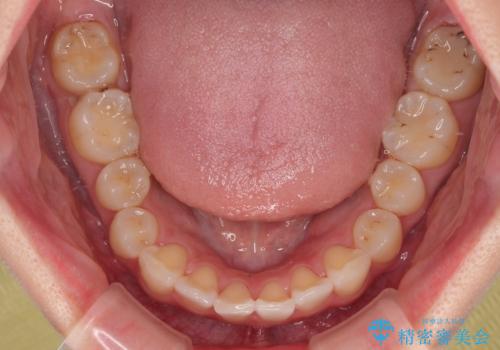

デコボコと咬み合わせを改善 インビザライン矯正治療

- 前歯のデコボコと突出感を気にして来院された患者様です。

極力目立たない装置を希望とのことで、インビザラインを用いて非抜歯で矯正治療を行うこととしました。

事前に親知らず2本を抜歯し、多少歯列を後方に移動できるように準備をした上で、なるべく歯と歯の間を削ることなくデコボコを解消できるように計画しました。